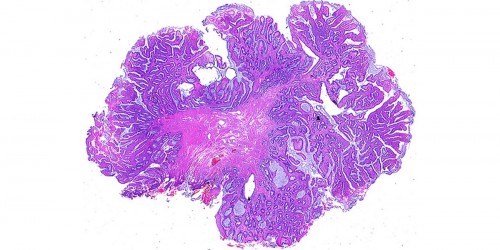

I did suffer from piles many years ago, I am wondering if they have returned?